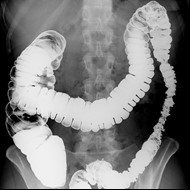

Przedstawiony obraz radiologiczny został zarejestrowany podczas badania jelita

Ilustracja do pytania 23

A. cienkiego po doustnym podaniu środka kontrastującego.

B. cienkiego po doodbytniczym podaniu środka kontrastującego.

C. grubego po doustnym podaniu środka kontrastującego.

D. grubego po doodbytniczym podaniu środka kontrastującego.